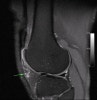

MRI : 슬개건염(Patellar tendonitis, Patellar tendinitis)